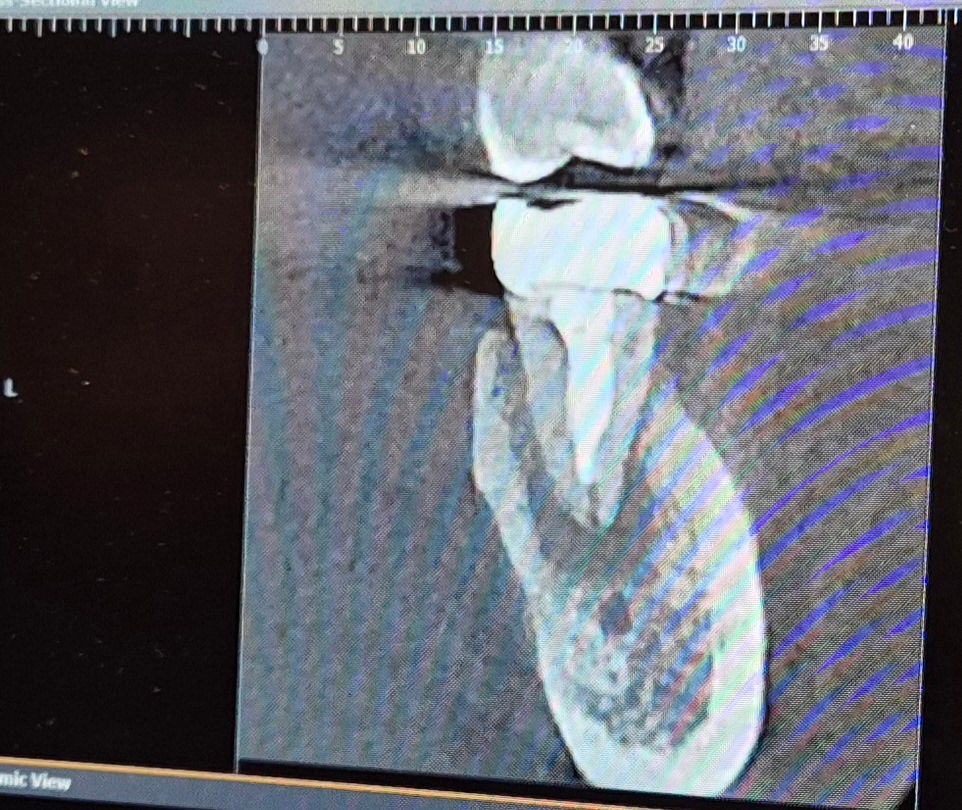

신경치료한 치과에서 엑스레이 씨티 모두 찍었는데요.

• 1번 째 사진

CT상으로 보면 치아 뿌리끝에 염증이 많이 진행된거 같습니다. 발치를 해야될 가능성이 높아 보입니다.

치아 뿌리 끄에 병소가 생긴것으로 보입니다.

신경치료를 하고 난 다음에 내부에 감염이 되었거나 뿌리끝의 파절로 인해서 감염이 된것으로 보입니다.

단순한 신경관의 감염이라면 재신경치료를 하면 되지만 뿌리이 파절이라면 발치를 하는것이 좋을수 있습니다.